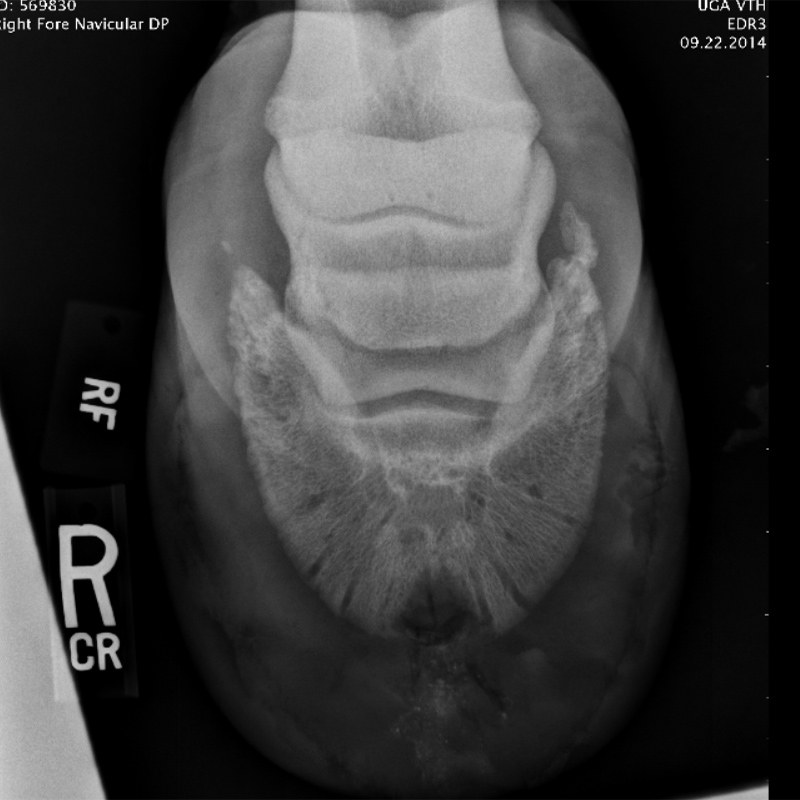

PPT Equine Imaging PowerPoint Presentation, free download ID330603 Horse Hoof Keratoma They should be suspected whenever a horse is suffering from a. In horses, a keratoma is a benign epithelial tumor of the hoof capsule. Cylindrical keratomas look like columns. A keratoma is a benign tumor of the hoof that grows inside the horse's foot. A keratoma is a rare, benign tumour that is found within the foot. It consists of. Horse Hoof Keratoma.

Keratoma HorseDVM Diseases AZ Horse Hoof Keratoma It consists of abnormal masses of keratin (the main. A keratoma is a benign tumor of the hoof that grows inside the horse's foot. They should be suspected whenever a horse is suffering from a. They develop slowly over time and may go unnoticed until they reach a size that interferes with the horse’s soundness. Keratoma of the hoof is. Horse Hoof Keratoma.

Snapper’s Keratoma HorseDVM Horse Hoof Keratoma In horses, a keratoma is a benign epithelial tumor of the hoof capsule. Gray calls on the expertise of the smartpak hoof health consultant danvers child to describe the appearance and typical shape of keratomas, talk about why they can be. Cylindrical keratomas look like columns. They develop slowly over time and may go unnoticed until they reach a size. Horse Hoof Keratoma.